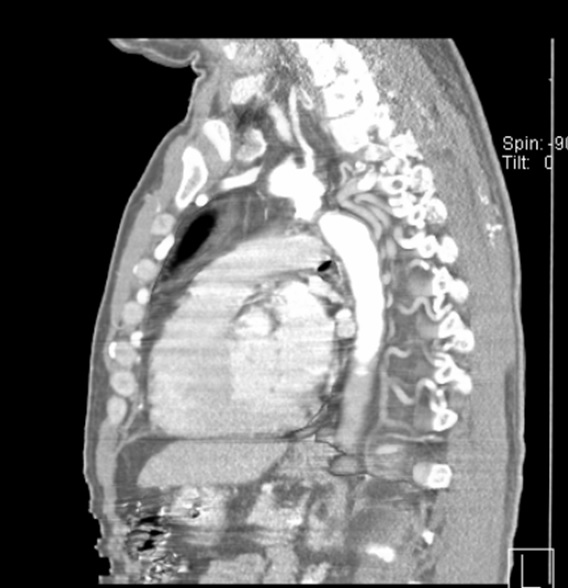

Femoral access cardiac catheterization showed complete occlusion of the thoracic descendent aorta distal to the left subclavian artery, without passage of the wire through the occlusion zone and with an 85 mm Hg gradient (Fig. 1A and 1B). Radial access cardiac catheterization showed significant proximal stenosis of the left anterior descending artery, circumflex artery, and right coronary artery.

Figure 1A and 1B: Thoracic aortogram. Aortic occlusion is evident.

Chest computed tomography (CT) angiography revealed atresia of the aortic arch distal to the origin of the left subclavian artery. The descending thoracic aorta was dilated distal to the occlusion zone and it was supplied by prominent collateral circulation from internal mammary arteries, intercostal arteries, and the vertebrobasilar system (Fig. 2). Cerebral magnetic resonance imaging (MRI) demonstrated diffuse lacunar infarcts with no evidence of berry aneurysms in the circle of Willis.